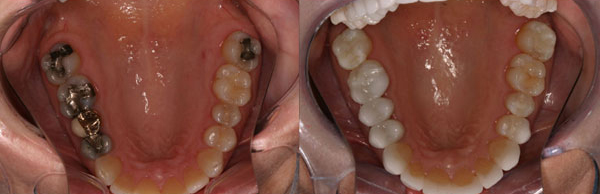

And cosmetic dentistry is a self-feeding phenomenon. We gauge the appearance of our smile against those around us. As more people get cosmetic dentistry, replacing metal amalgam fillings or gold crowns with more attractive ceramic restorations, our sense of what makes a smile attractive shifts. Where people just a few years ago might have thought that metal fillings were normal, today most look at this as an unacceptable alternative. You don’t want to be the only one with visible fillings if you can help it.

If you’ve grown tired of your old metal restorations, now is a great time to remove them and replace them with ceramic restorations.